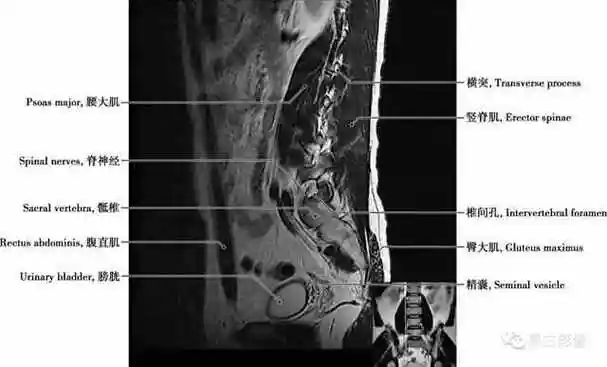

详细的腰椎mri正常解剖图谱,带标注,值得收藏!

第三节 腰椎的mri解剖